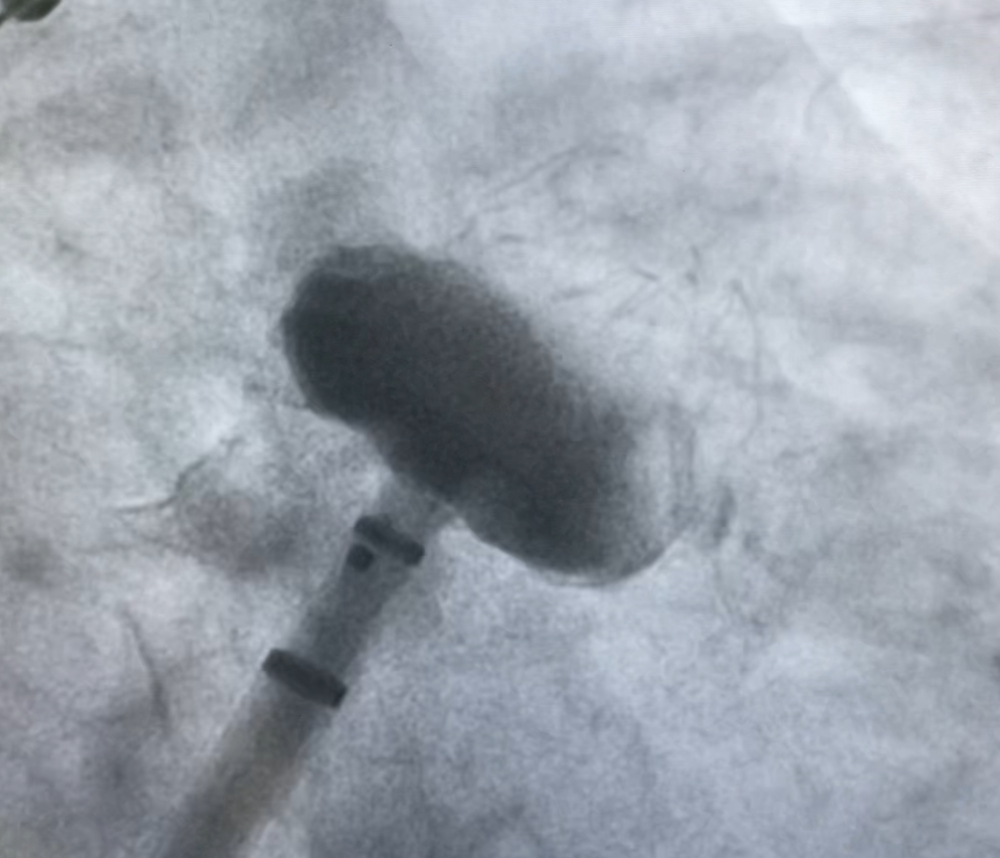

术中DSA造影测量图

术中DSA影像图